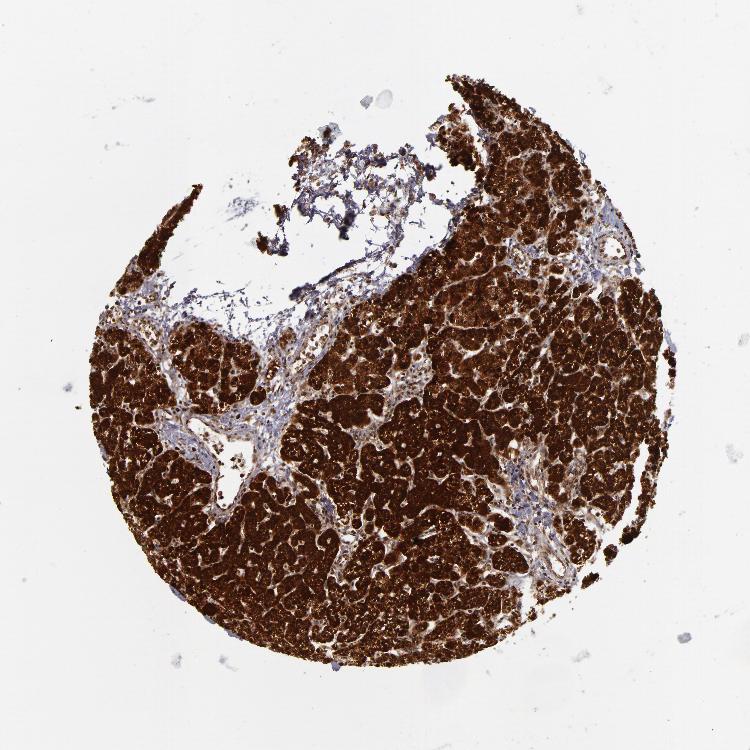

PARATHYROID GLAND - Antibody stainingi

Antibody staining in the annotated cell types in the current human tissue is reported as not detected, low, medium, or high, based on conventional immunohistochemistry profiling in selected tissues. This score is based on the combination of the staining intensity and fraction of stained cells.

Each image is clickable and will lead to virtual microscopy that enables deeper exploration of all samples and also displays staining intensity scores, fraction scores and subcellular localization as well as patient and tissue information for each sample.

Antibody HPA002185Antibody CAB017787

Glandular cells HighHigh